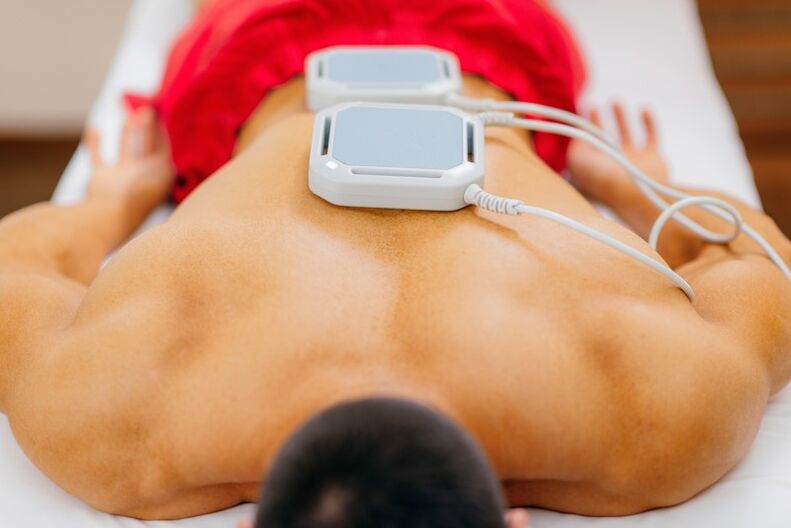

Physiotherapeutische Behandlung

Diese Behandlung wird verordnet, nachdem die Schmerzen medikamentös gelindert wurden. Physiotherapeutische Verfahren aktivieren den Gewebestoffwechsel, beschleunigen die Geweberegeneration und stoppen die weitere Zerstörung von Knochen- und Gelenkgewebe.

Die Liste der Verfahren lautet wie folgt:

- Elektrophorese. Gewährleistet eine schnelle Abgabe der medizinischen Lösung an die Schmerzlokalisationsstellen. Der Vorgang sieht so aus: Mit einer Medikamentenlösung getränkte Wattepads werden auf den unteren Rücken aufgetragen. Oben sind spezielle Platten befestigt, die elektrische Stromentladungen abgeben. Unter dem Einfluss von Impulsen dringt die Lösung in den Entzündungsbereich ein;